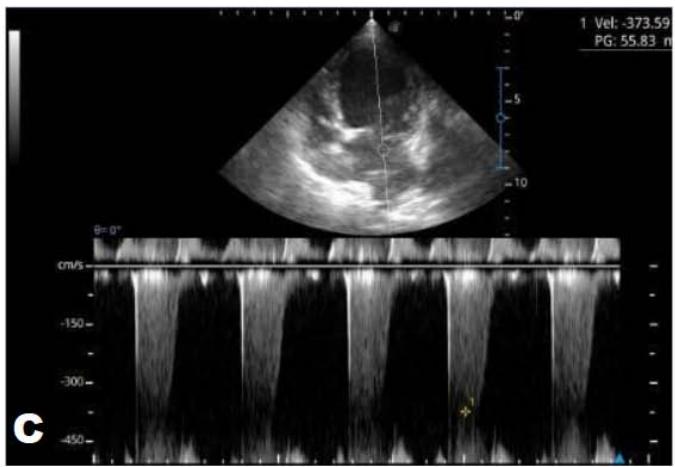

Figure 5: Echocardiogram (January/2023): observed increase in the left atrium and ventricle; thickened/degenerated/prolapsed mitral valve (A); observed in Doppler study, systolic turbulent flow within the left atrium characterizing severe mitral valve insufficiency (B). Hemodynamic assessment - Maximum velocity gradient mitral regurgitation: $3.74 \, \text{m/s} / 55.83 \, \text{mmHg}$: Observed left ventricular diastolic dimension above standard limits, with normal systolic function parameters, characterizing systolic dysfunction; preserved diastolic function

In 2023, the animal returned and repeated only the ECHO (Figure 5), where no significant changes were observed during this period, except for a structural change in the mitral valve, identifying a prolapse and increase in the left ventricular diastolic dimension, with systolic function parameters, characterizing systolic dysfunction; diastolic function remained preserved.